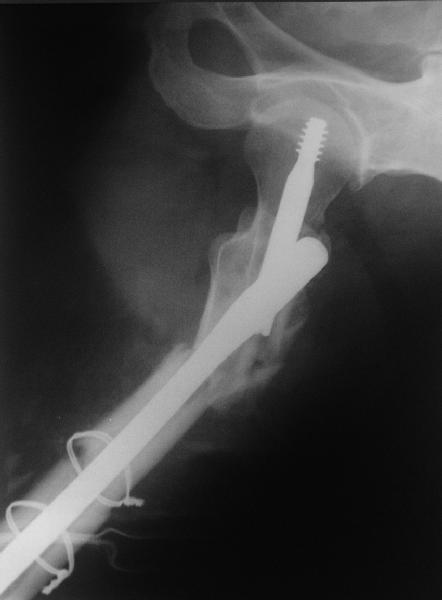

Изначально была выбрана не правильная точка введения стержня, в связи с чем в конце, я подчеркну, в конце операции произошло из-за напряжения между прокимальным концом канала бедра и стержнем разрушение в/3 бедра.

Проволока наложена потому, что при введении штифта не прошли эту зону римером и произошли сколы на концах отломков.

Под ЭОП во время операции такого смещения не было. Мы бы конечно не отпустили этого больного с такой картиной (сами бы что-то сделали или к вам отпр).

Зона раскола во время моей ревизии проходит по боковой поверхности как раз в зоне введения шеечного винта (картина как топор разрубил полено на две равных части, можа сделать КТ?)

ВБ> Длинная гамма?

ВБ> Зона раскола во время моей ревизии проходит по боковой поверхности как

ВБ> раз в зоне введения шеечного винта (картина как топор разрубил полено

Зона введения и вообще латеральная стенка тут не имеет значения, поскольку угловая стабильность обеспечивается самим фиксатором.

В общем, сделали. См. приложение.

Длина и из-за этого ось получились не совсем такие, как хотелось бы, все-таки срок после той операции уже 6 недель. Может быть, стоило провести дистракцию аппаратом неделю-другую. Заранее спасибо за комментарии и критику.